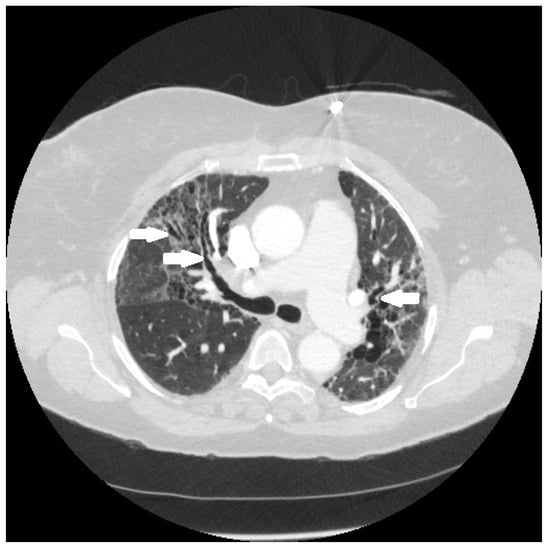

Figure 4.

Chest CT image of a patient with pulmonary sarcoidosis, demonstrating subpleural opacities from granulomatous inflammation (arrows).